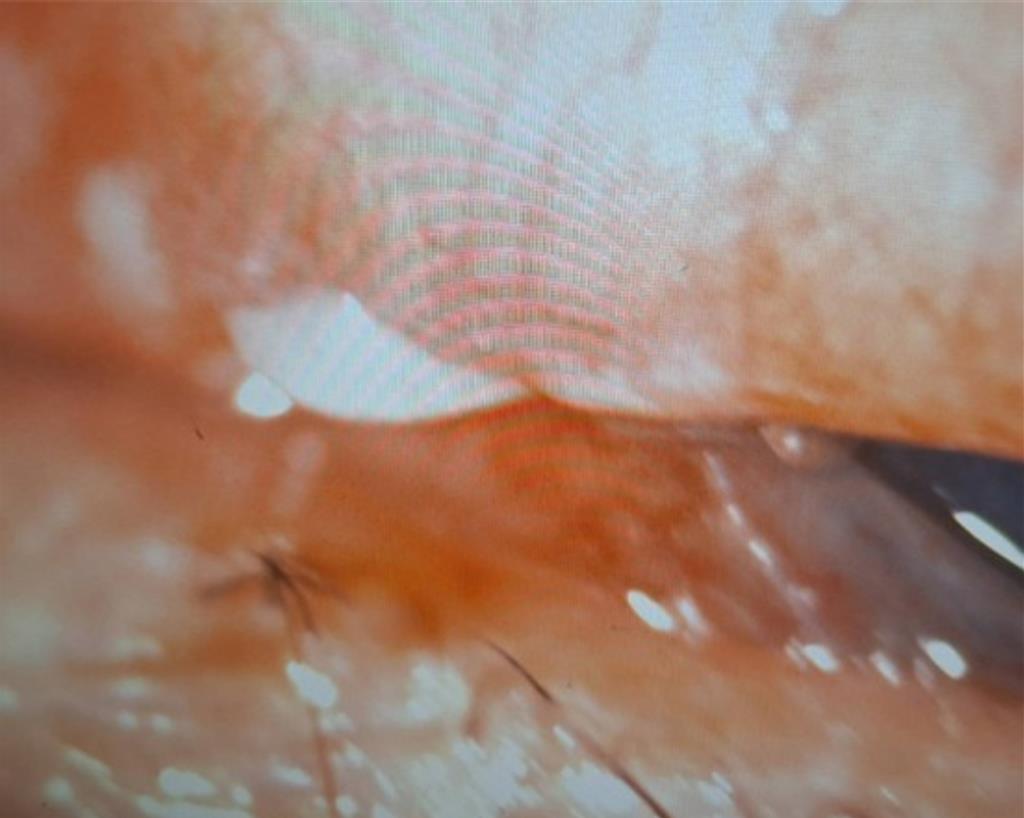

高雄林姓女子遭友人飼養的馬爾濟斯咬傷右眼,上眼皮嚴重撕裂傷,狗牙碎片還插在右眼瞼結膜上,幸虧經緊急治療後,目前已無大礙。(達特楊眼科聯盟提供/洪浩軒高雄傳真)

洪啟庭指出,經檢查,發現造成大量流血的部位為右眼上眼皮,約有5公分撕裂傷,立刻予以縫合止血,隨後檢查視力、角膜與鞏膜均無異狀,但有明顯結膜下出血與結膜水腫,且林女仍有嚴重異物感,翻開上眼皮再次檢查,赫然發現有白色小碎片被插在右眼瞼結膜上,緊急取出異物後,證實是馬爾濟斯牙齒碎片,坦言「狗牙卡人眼」實屬罕見,經後續治療,目前林女右眼已恢復正常無大礙。